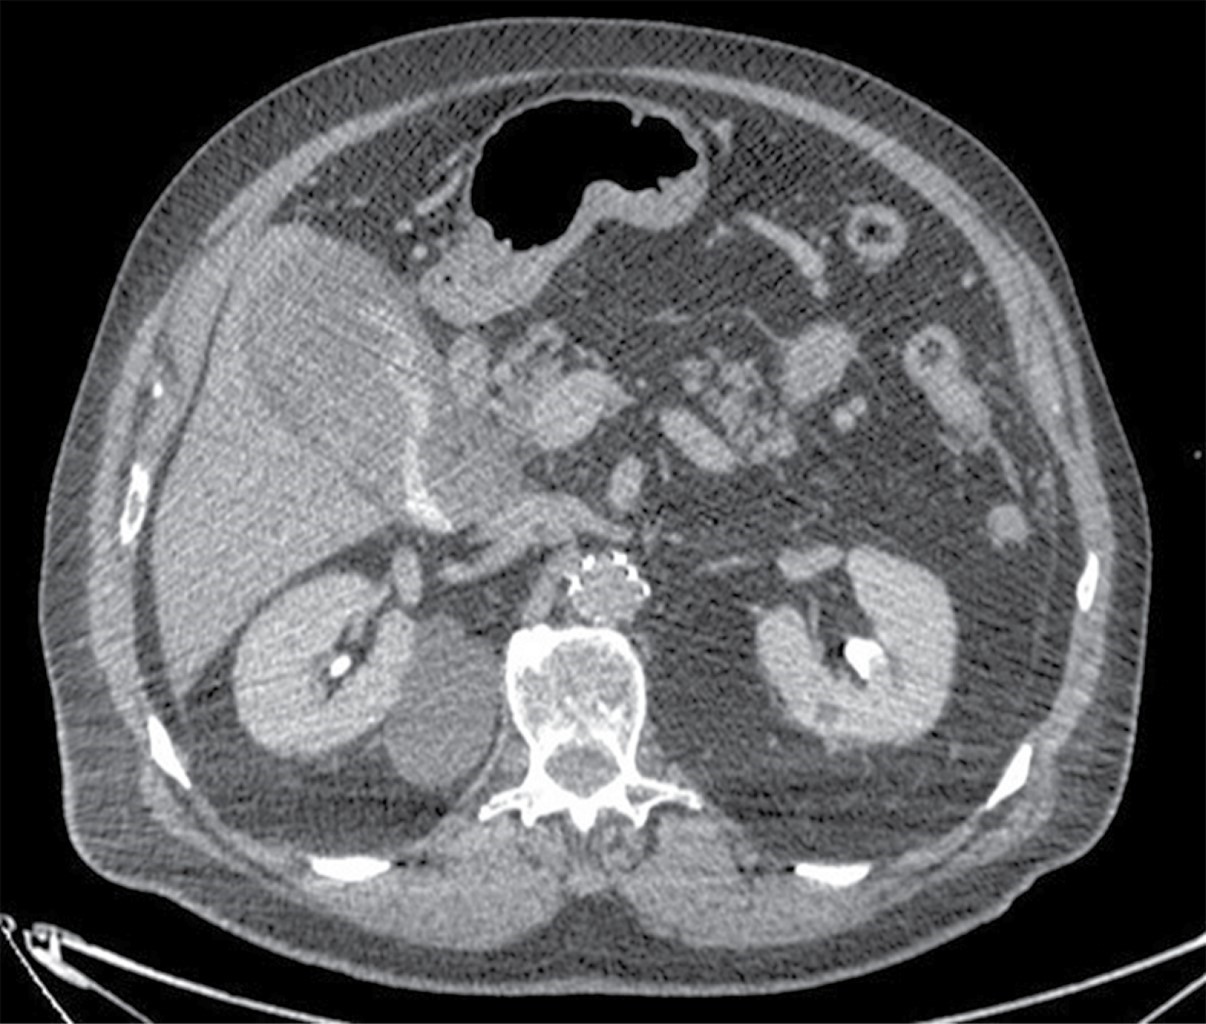

Paciente masculino de 77 años de edad con el antecedente de cardiopatía isquémica no especificada en 2001, tratada con la colocación de dos stents coronarios en acompañamiento con ácido acetilsalicílico; además de tromboembolia pulmonar en 2009, en tratamiento con acenocumarol; y aneurisma aórtico tratado en 2012 con stent aortoiliaco. Acudió a urgencias por presentar dolor abdominal difuso con 12 horas de evolución e intensidad 8/10 en escala de EVA, sin irradiaciones, sin exacerbantes, con náusea sin vómito, se automedicó con butilhioscina y presentó mejoría parcial de 6/10 en escala de EVA. A la exploración física se encontró Glasgow de 15, saturación a 90%, hipertensión arterial 211/116, temperatura de 36 oC, frecuencia respiratoria 13 y abdomen globoso con datos de irritación peritoneal. Los laboratorios reportaron hemoglobina 18.5 g/dl (14.5-18.5), hematocrito 54.4% (42.0-50.0), leucocitos 13.9 103/μl (4.8-10.0), plaquetas 170 103/μl (150-450), TP 42.34 segundos (9.60-12.00), INR 4.33 (0.90-1.20) y TTPa 34 segundos (22-35). Por los antecedentes médicos y quirúrgicos, se decidió realizar angiotomografía computarizada, que reportó sangrado activo hacia la luz de la vesícula biliar (Figuras 1 y 2), hemoperitoneo, stent aortoiliaco permeable y en situación normal, y arteria mesentérica inferior obliterada. Se decidió su ingreso a Terapia Intensiva para estabilización hemodinámica, se transfundieron seis Octapro® (factores de la coagulación IX, II, VII y X), dos paquetes globulares, cuatro plasmas y tres aféresis plaquetarias, además se realizó colecistectomía laparoscópica dos horas después de su ingreso hospitalario.

Los hallazgos ecográficos de colecistitis hemorrágica pueden mostrar engrosamiento de la pared de la vesícula biliar, membranas intraluminales y material ecogénico intraluminal no móvil, ni ensombrecido. Los hallazgos de la tomografía computarizada (TC) pueden demostrar extravasación de contraste, alta atenuación dentro de la luz de la vesícula biliar y estratificación fluido-fluido.10

La TC con fase arterial puede ayudar a diagnosticar y demostrar los hallazgos característicos del engrosamiento de la pared, de la vesícula biliar distendida y los materiales heterogéneos en su interior, además de la extravasación activa del contraste en el lumen de la vesícula biliar.11

Figura 2